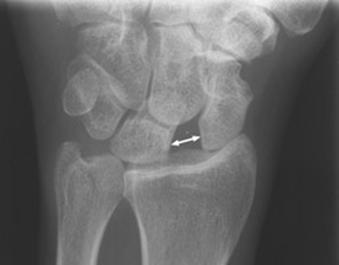

Largirea articulatiei scafo-lunare Fractura

Galeazzi

Semnul Terry Thomas

Fractura Galeazzi Fractura Monteggia